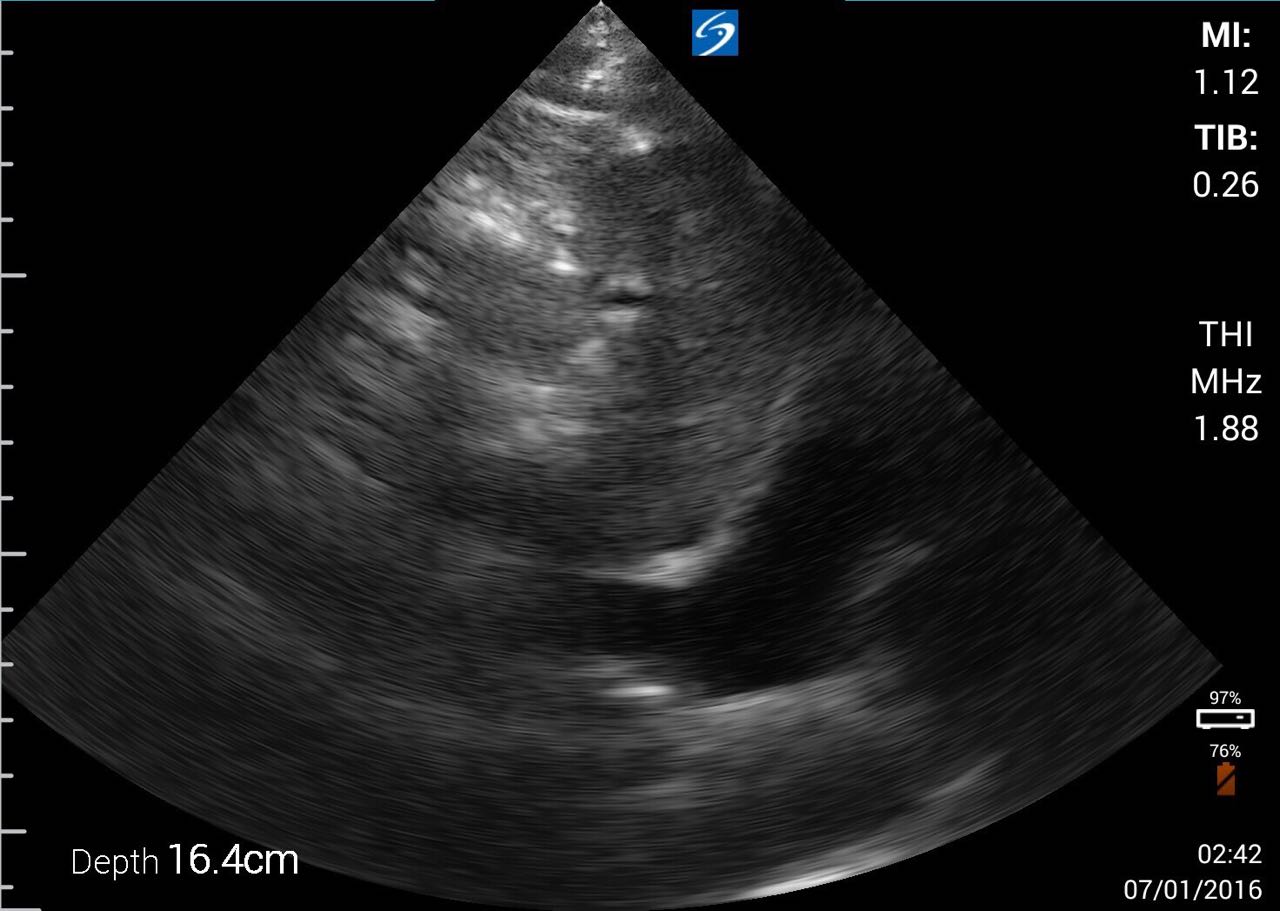

下載的畫面: IVC

下載的影片: IVC (錄影的秒數可以自定)